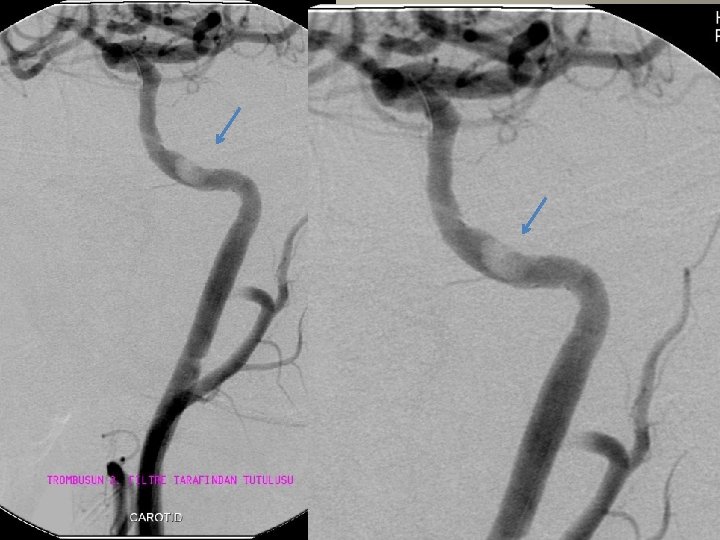

Neden stent? TANDEM lezyon

Neden stent? Distal emboli koruma

Neden stent? Eş zmanlı komplikasyon idaresi